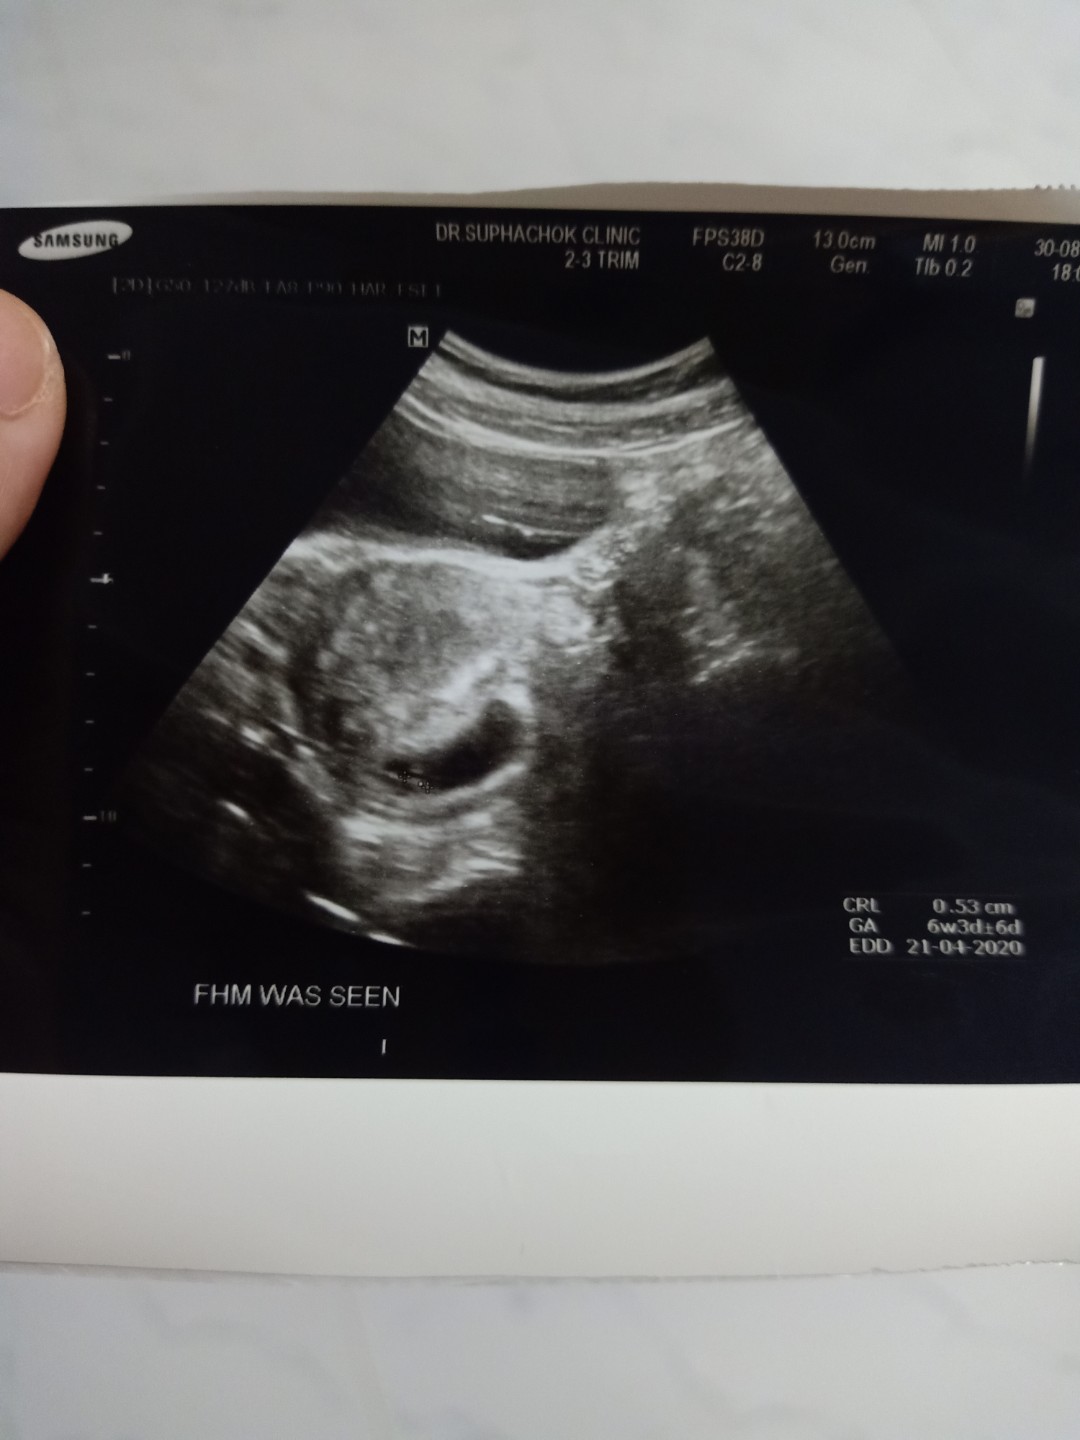

6 สัปดาห์ 3 วัน ขนาดตัวอ่อน 0.56cm ถือว่าปกติไหมค่ะ

ปกติจ้า 6 week 3 day 0.53